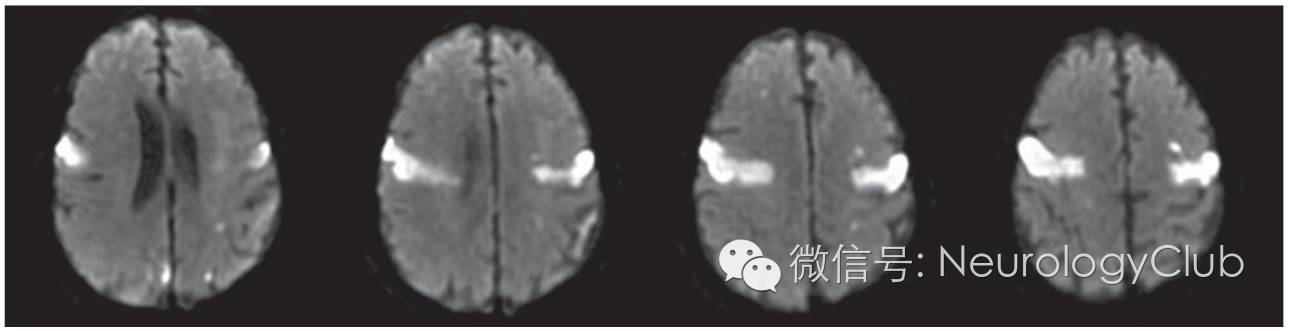

(图3:DWI上可见双侧前岛盖梗死)